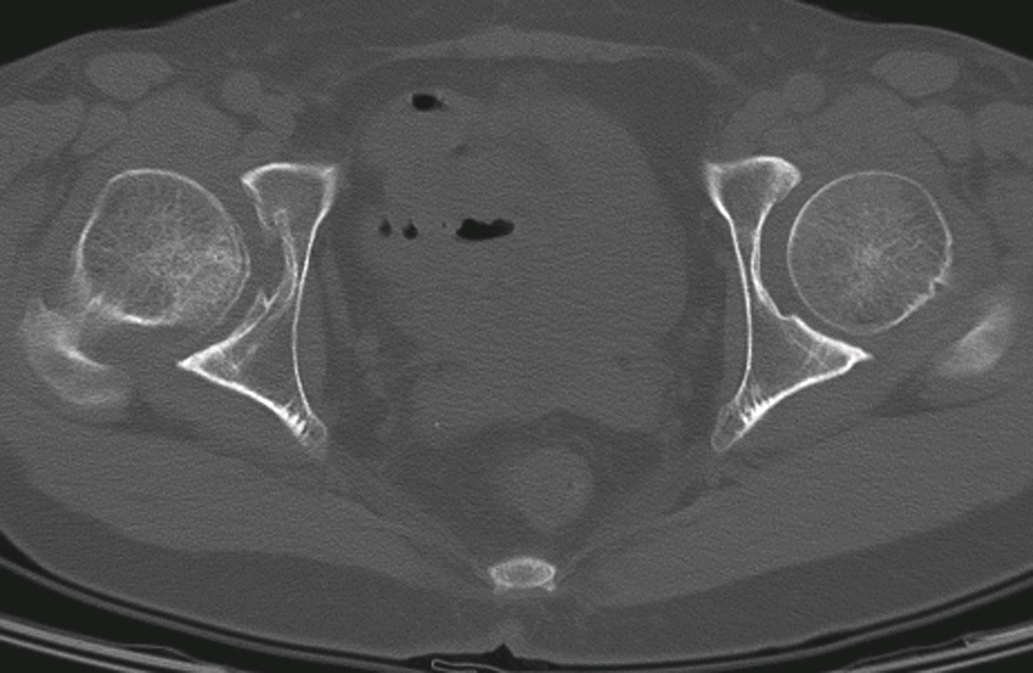

双侧髋臼发育不良伴退行性骨关节病

CT平扫,示双侧髋臼前断面角变小,头臼包容差,髋臼及股骨头轻度骨质增生

髋臼前断面角变小,后断面角小于正常;股骨头顶部层面见不到顶唇,且前后唇变短;股骨头稍向前方移位;伴发关节退行性改变,可见关节间隙变窄,关节面硬化并关节面下囊变,同时髋臼前唇和上部边缘可见骨质增生。有时可合并关节积液。